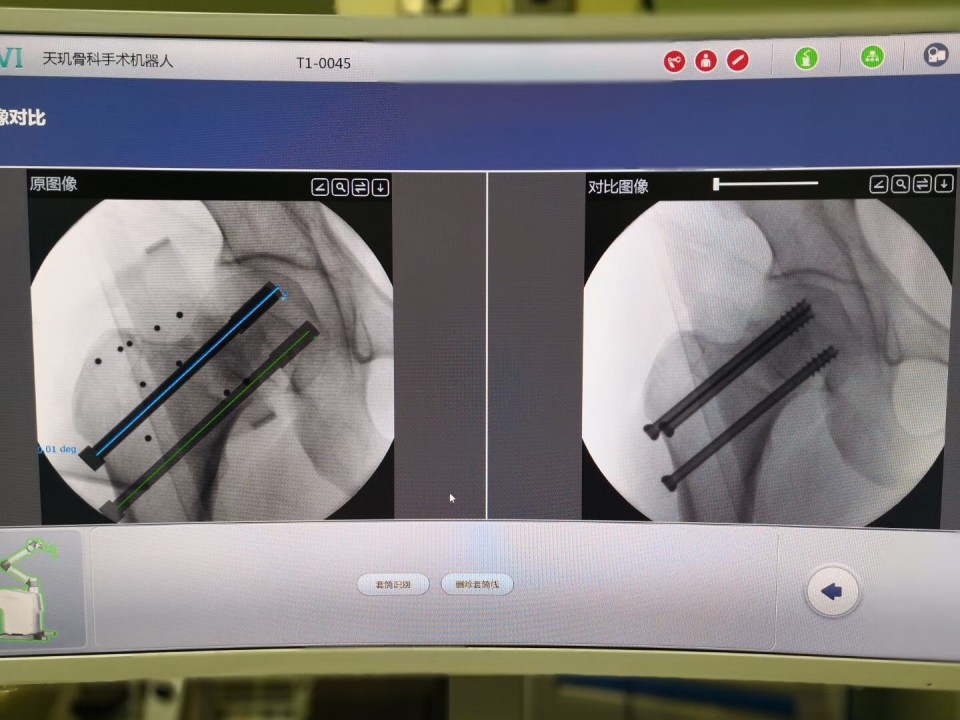

此次“天玑”骨科机器人被应用于两位骨折患者,首台是一位骨盆骨折患者,由于骨盆位置深,解剖关系复杂,传统手术需切开复位后钢板固定,创伤较大,手术时间长,容易出血,术后并发症多,而借助“天玑”机器人,可以闭合复位,并应用最新的闭合通道螺钉技术固定骨折,极大地减少了手术时间与手术创伤;对于另一位股骨颈骨折患者,有着“透视眼”、“稳定手”之称的“天玑”再次不负众望,利用计算机进行精确的置钉规划,使得螺钉分布更合理,固定更确切,更有利于骨折的愈合,从而减少股骨头坏死的发生率。

两台手术由创伤骨科七东科主任王刚,主治医师张琦与住院总医师章乐成共同完成,骨折复位后,影像扫描、数据传输到进钉点规划及螺钉置入的复杂过程,仅用半个小时,标志着我院创伤骨科水平在省内领先的基础上,进一步提升了在创伤救治能力上的优势。